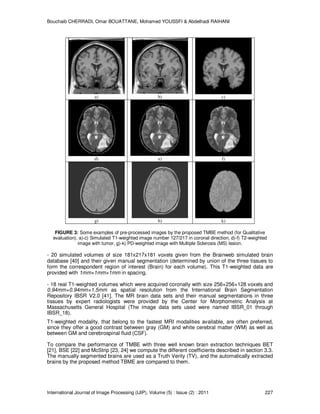

To prove the effectiveness of the proposed method for the skull stripping problem we have

massively experiment TMBE using simulated and real MR image data in different modalities of

acquisition. The figure 3 shows some samples of pre-processed images.

FIGURE 3: Some examples of pre-processed images by the proposed TMBE method (for Qualitative

evaluation). a)-c) Simulated T1-weighted image number 127/217 in coronal direction, d)-f) T2-weighted

image with tumor, g)-k) PD-weighted image with Multiple Sclerosis (MS) lesion.

- 20 simulated volumes of size 181x217x181 voxels given from the Brainweb simulated brain

database [40] and their given manual segmentation (determined by union of the three tissues to

form the correspondent region of interest (Brain) for each volume). This T1-weighted data are

provided with 1mm×1mm×1mm in spacing.

- 18 real T1-weighted volumes which were acquired coronally with size 256×256×128 voxels and

0.94mm×0.94mm×1.5mm as spatial resolution from the International Brain Segmentation

Repository IBSR V2.0 [41]. The MR brain data sets and their manual segmentations in three

tissues by expert radiologists were provided by the Center for Morphometric Analysis at

Massachusetts General Hospital (The image data sets used were named IBSR_01 through

IBSR_18).

T1-weighted modality, that belong to the fastest MRI modalities available, are often preferred,

since they offer a good contrast between gray (GM) and white cerebral matter (WM) as well as

between GM and cerebrospinal fluid (CSF).